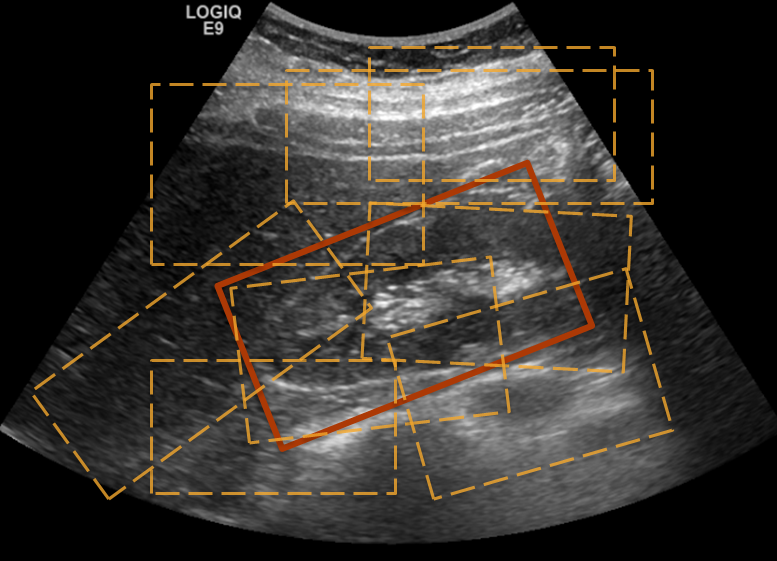

To build our binary classification models from training images, we swept the field of view (FOV) to generate many overlapping patches of varying sizes (see Fig. 1) that satisfied clinical guidelines on average adult kidney dimensions and aspect ratio [8]. We downsampled these ROIs to a common size and were further binned into two classes based on their overlap with ground truth annotations. We used Dice similarity coefficient (DSC) as the metric and a threshold of 0.8 (based on visual and clinical feedback) was used to generate positive and negative class samples. This was followed by feature extraction and model building.

Figure 1: (a) Sample Generation (b) Positive patches (c) Negative patches